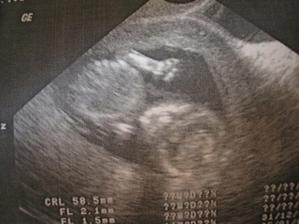

Daníček se narodil 28.12.2007 v 0:40 císařským řezem, vážil 4,53kg a měřil 53cm, žádnej drobeček to nebyl a není, papá jako o závod a váha přibývá a přibývá....🙂)